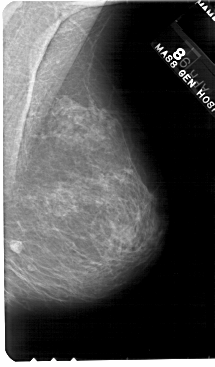

A_1562_1.LEFT_MLO

LEFT_MLO LINES 5491 PIXELS_PER_LINE 3541 BITS_PER_PIXEL 12 RESOLUTION 43.5 OVERLAY